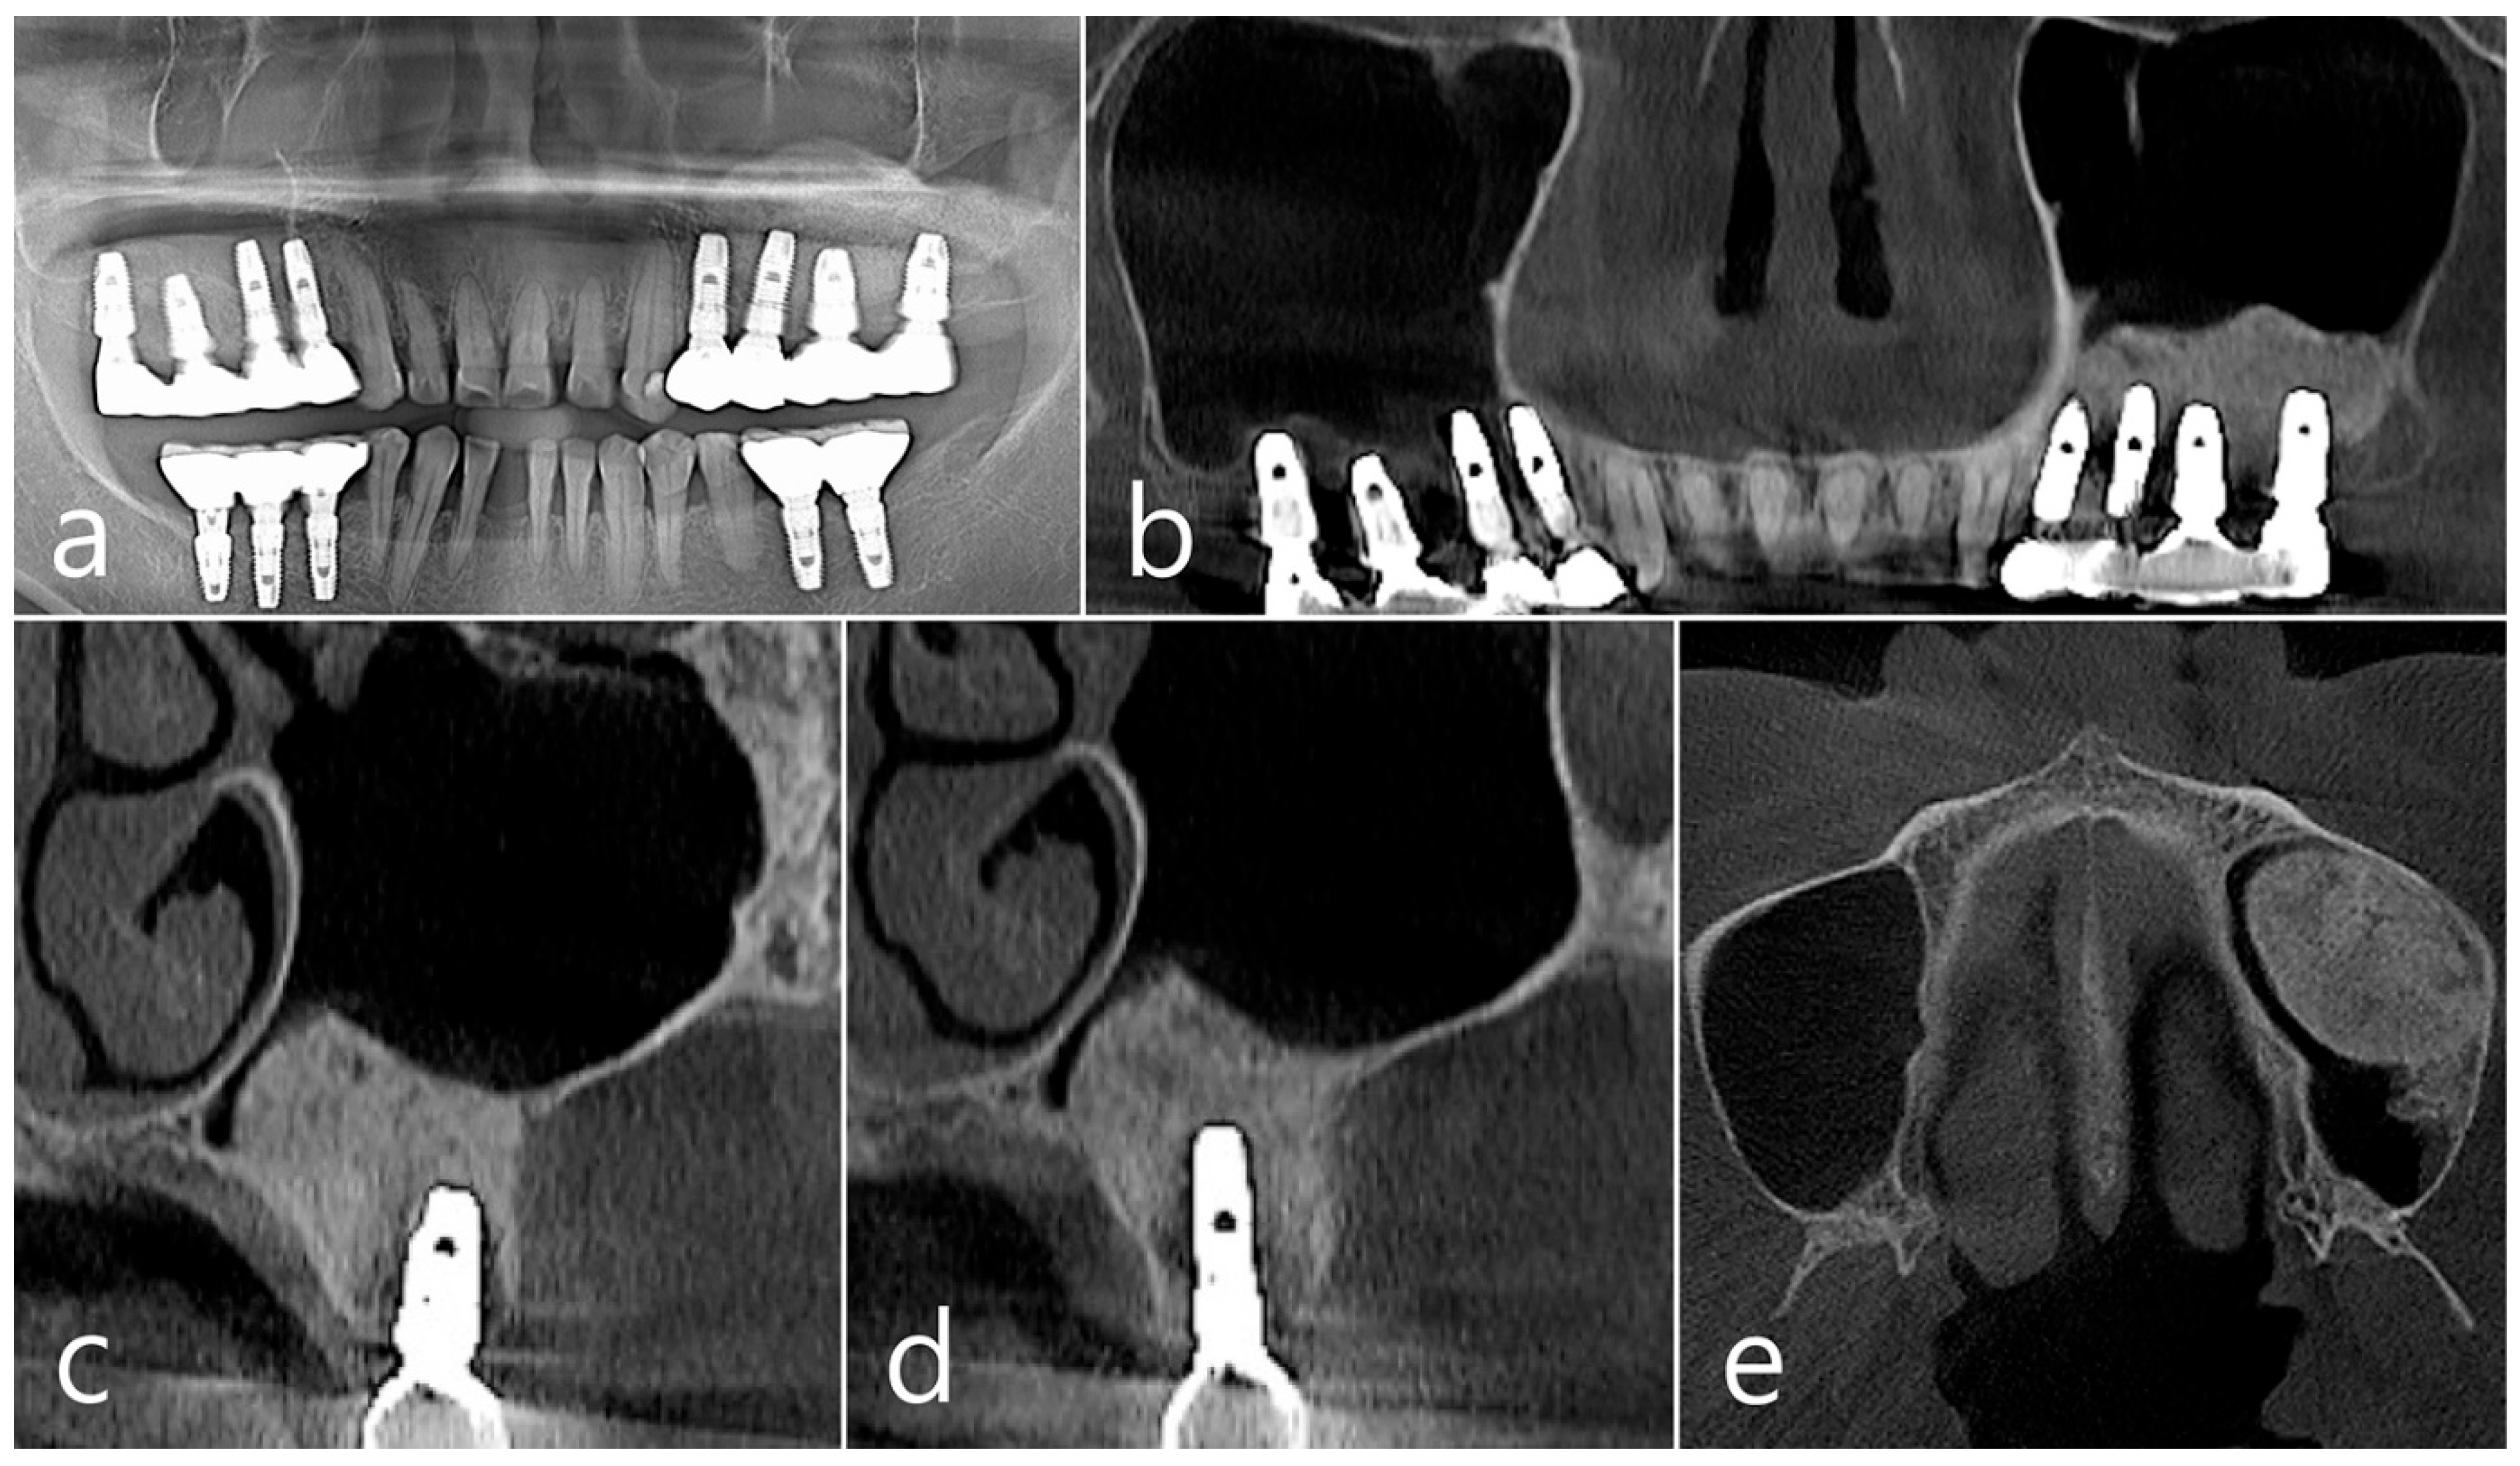

In the panoramic radiography and CBCT images taken after the prosthesis was delivered, no unusual radiographic image was observed at the bone graft site in the left maxillary sinus (Figure 3a,b). In the coronal images of the CBCT scans in #25 and #26 implants, no specific finding was found at the bone graft site of the maxillary sinus, and there was no thickening of the sinus membrane (Figure 3c,d). A well-consolidated sinus graft was observed on the axial image of CBCT (Figure 3e). The patient was checked up twice a year, and panoramic radiography and CBCT were taken 1 year after prosthesis delivery. Radiolucent images were observed around implants #25 and #26 (Figure 4a–d). A circular radiolucent image was observed in the axial image of CBCT (Figure 4e).

Figure 3. (a,b) In the panoramic radiography and CBCT images taken after the prosthesis was delivered, no special radiographic image was observed at the left sinus augmented site; (c,d) In coronal images of CBCT scanned in #26 and #25 implants, a homogenous radiographic density was observed at the sinus augmented site, and there was no thickening of the sinus mucosa; (e) A well-augmented sinus graft was observed in CBCT axial image.

Figure 4. (a,b) In the panoramic radiography and CBCT images taken 1 year after prosthesis delivery, unusual radiolucent images were observed around implants #25 and #26; (c,d) Radiolucent images around #26 and #25 implants were observed. The buccal cortical plate was lost. However, the appearance of the sinus graft was well maintained, and sinus mucosal thickness was normal; (e) A circular radiolucent finding was observed in the axial image of CBCT.